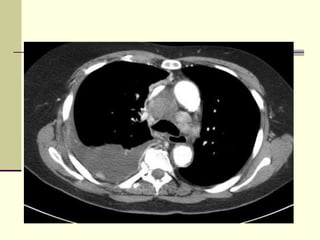

 CT scan